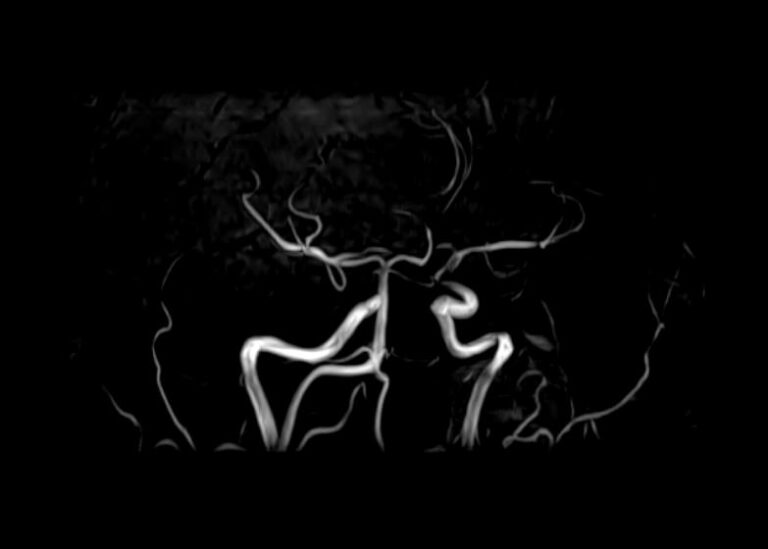

Кроме того, в области шеи проходят крупные кровеносные сосуды, кровоснабжающие все структуры головного мозга и мягких тканей головы. К ним относятся плечеголовной ствол, сонные и позвоночные артерии, которые далее в полости черепа соединяются между собой в Виллизиев круг. Это анатомическое образование позволяет компенсировать мозговой кровоток при патологических состояниях.

Сканирование проводится на современном высокопольном магнитно-резонансном томографе закрытого типа TOSHIBA VANTAGE TITAN 1,5 Тесла. Магнитно-резонансный томограф производит послойное сканирование исследуемой зоны в разных плоскостях, затем при помощи компьютерных программ преобразует полученные данные в трехмерные изображения. При этом кровеносная система реконструируется как вместе с окружающими тканями, так и отдельно без них.

• участки сужения, извитость, образование петель и перегибов сосудов;

• ангиомы, сосудистые мальформации;